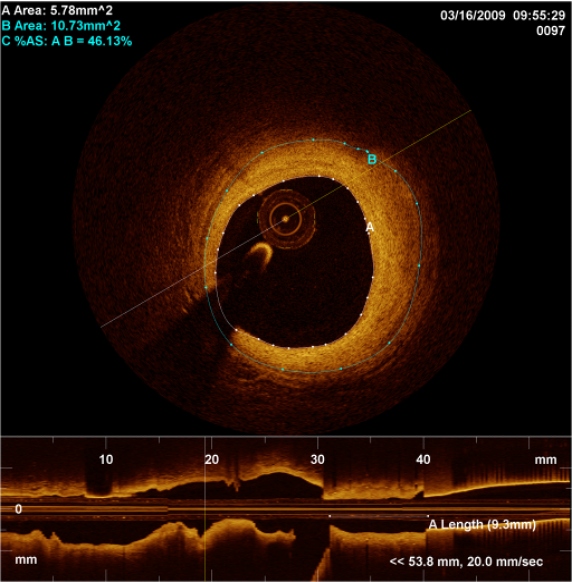

Από την άλλη, η  οπτική συνεκτική τομογραφία χρησιμοποιεί φως μικρής συνοχής (συνήθως υπέρυθρο φως)  για τη λήψη εικόνων υψηλής ανάλυσης από το εσωτερικό των αγγείων. Αυτή η τεχνική παρέχει λεπτομερή απεικόνιση της δομής της πλάκας και της επιφάνειας του ενδοθηλίου. Έτσι, καθίσταται ιδανική για την αξιολόγηση μικρών βλαβών και τη διάγνωση ενδοστεφανιαίων θρόμβων ή δυσλειτουργιών των stent.

OCT